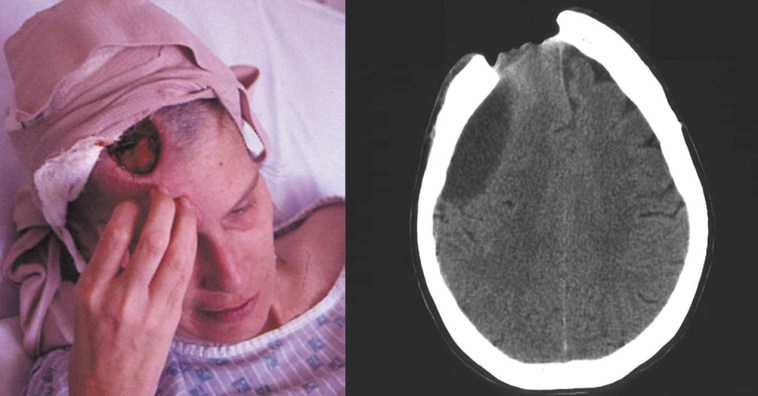

Этот любопытный клинический случай 2001 года был опубликован в журнале Pain. У 39-летней Мэри Эллен Нильсен начался опоясывающий лишай и были назначены противовирусные препараты, которые вызвали у неё нестерпимый зуд при полном отсутствии иных болевых ощущений. Примерно через год с ней случилось странное. Однажды ночью Мэри проснулась с ощущением того, что она уже не просто чешет голову. Мэри Эллен Нильсен прочесала свой череп насквозь, не заметив этого.

остеомелит у нее был в той области черепа. та что не щитаеца, кость мягонькой была